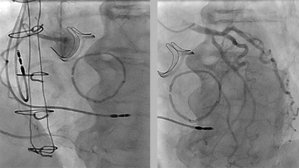

Ce patient de 86 ans est hospitalisé pour des lésions dermatologiques aspécifiques. Il présente plusieurs facteurs de risque cardiovasculaire : un tabagisme ancien, un diabète de type 2, de l’hypertension, une dyslipidémie et un surpoids. Il est également atteint d’une surdité non appareillée et d’une maladie aortique.